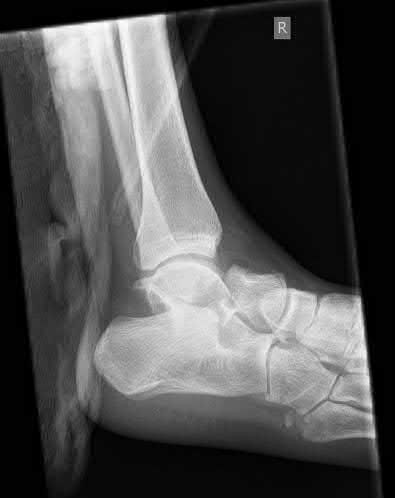

Figures A to C show radiographs of a 70 year-old male who fell on the ice 5 days ago. He could initially walk after the fall, but he is now unable to weight-bear on the leg due to pain. Physical examination shows diffuse ankle swelling, with no medial sided ankle tenderness. He is neurovascularly intact. The patient does not smoke and has no medical history. A gravity stress radiograph is demonstrated in Figure

D. After closed reduction, there is 2 mm of fracture displacement, no talar shift and the talocrural angle = 83 degrees. What is the most appropriate treatment?

Figure A demonstrates an AP radiograph of a Weber B fibula fracture with minimal medial clear space widening.

Figure B demonstrates a mortise radiograph of a Weber B fibula fracture with a congruent mortise.

Figure C demonstrates a lateral radiograph of a Weber B fibula fracture with a congruent mortise.

Figure D demonstrates a stress radiograph with minimal medial clear space widening.